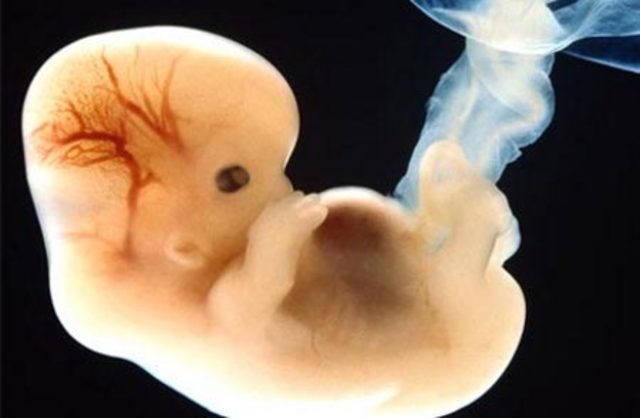

• 3 Semana

3 Semana

*Se forma lo que será el corazón, a través de una reacción en cadena de una célula que se contrae y hará latir a las demás a su alrededor.

*El embrión tiene un conato de sistema nervioso y corazón.